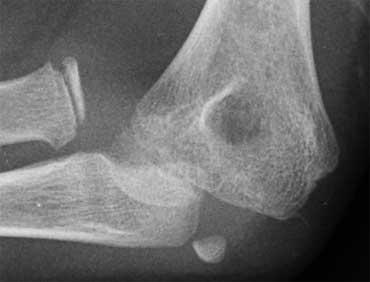

Gãy chỏm con

Trong khi gãy lồi cầu ngoài xảy ra ở trẻ em trong độ tuổi từ 4 – 10 tuổi, gãy chỏm con đơn độc được gặp ở trẻ em trên 12 tuổi.

Gãy xương chỏm con là không phổ biến.

Sự xoay của mảnh gãy tạo ra hình ảnh điển hình trên phim X-quang (mũi tên).